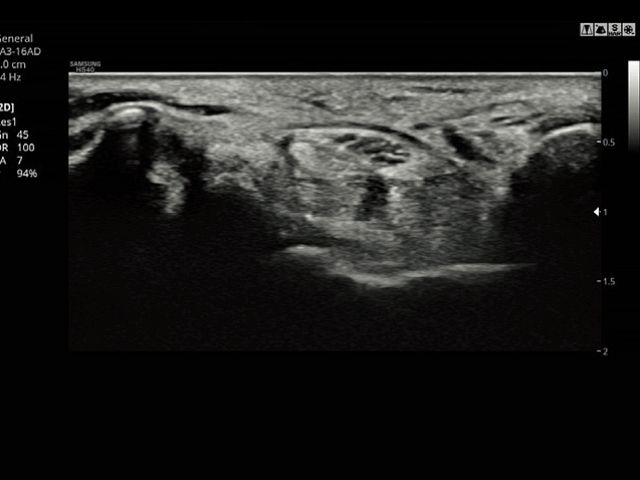

ClearVision provides clearer tissue boundaries using the noise reduction filter and generates sharp 2D images. It reduces halo artifact that occurs when the tissue contour is enhanced, and removes noises on the tissue boundaries.

MultiVision controls ultrasound beam electronically by steering, and compounds many scan lines for better image. MultiVision provides remarkable spatial and contrast resolution with even greater artifact suppression than ever before.

LA3-16ADApplication:Small parts, Vascular, Musculoskeletal, Abdomen, Obstetrics, Gynecology, Pediatric, Emergency |